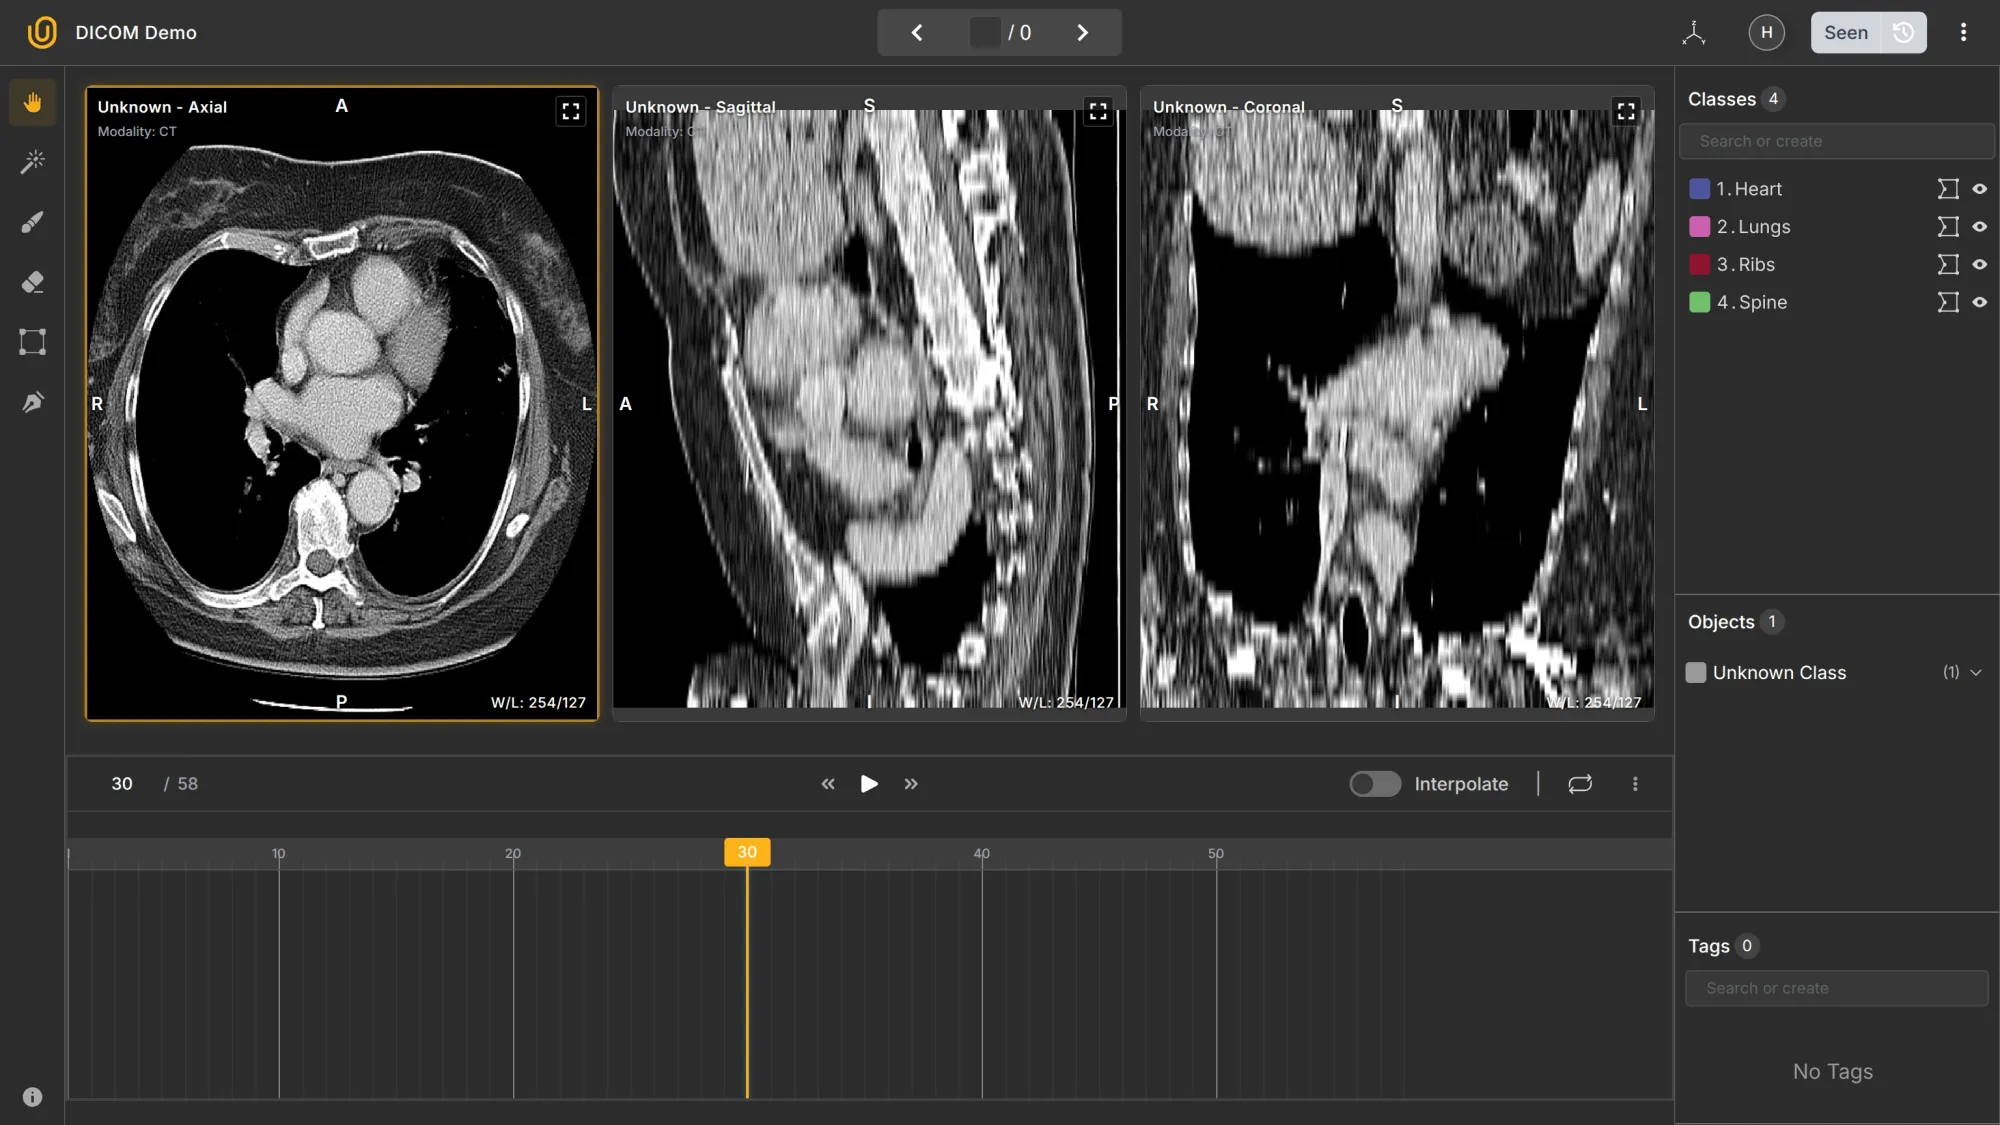

- Multi-slices → A DICOM study can contain dozens or hundreds of consecutive 2D slices of the same body region (e.g., 58 slices through the chest).

- 2D and 3D → Each slice is 2D, but when combined, they form a 3D volume. Annotation tools can reconstruct or navigate through that volume interactively.

- Multi-planes → You can view the same dataset in different planes:

- Axial (top-down)

- Sagittal (side)

- Coronal (front)

Together, these make DICOM data volumetric and spatially consistent; that’s why it’s used for medical imaging rather than formats like PNG or JPEG.

Although the DICOM format is not strictly necessary for training computer vision algorithms, it's highly beneficial to preserve it for data labeling purposes.

We are certain that 95% of the readers will have no idea what is going on. It is highly probable that most people, even data annotators without medical knowledge, freeze when they see the annotation dashboard for medical labeling:

For starters, what is Axial, Sagittal, and Coronal? What is interpolation in this context? 3D and 2D? Multilayers? 58 frames in the Axial section? Understanding the conventions, let alone annotating medical images, is not an easy task.